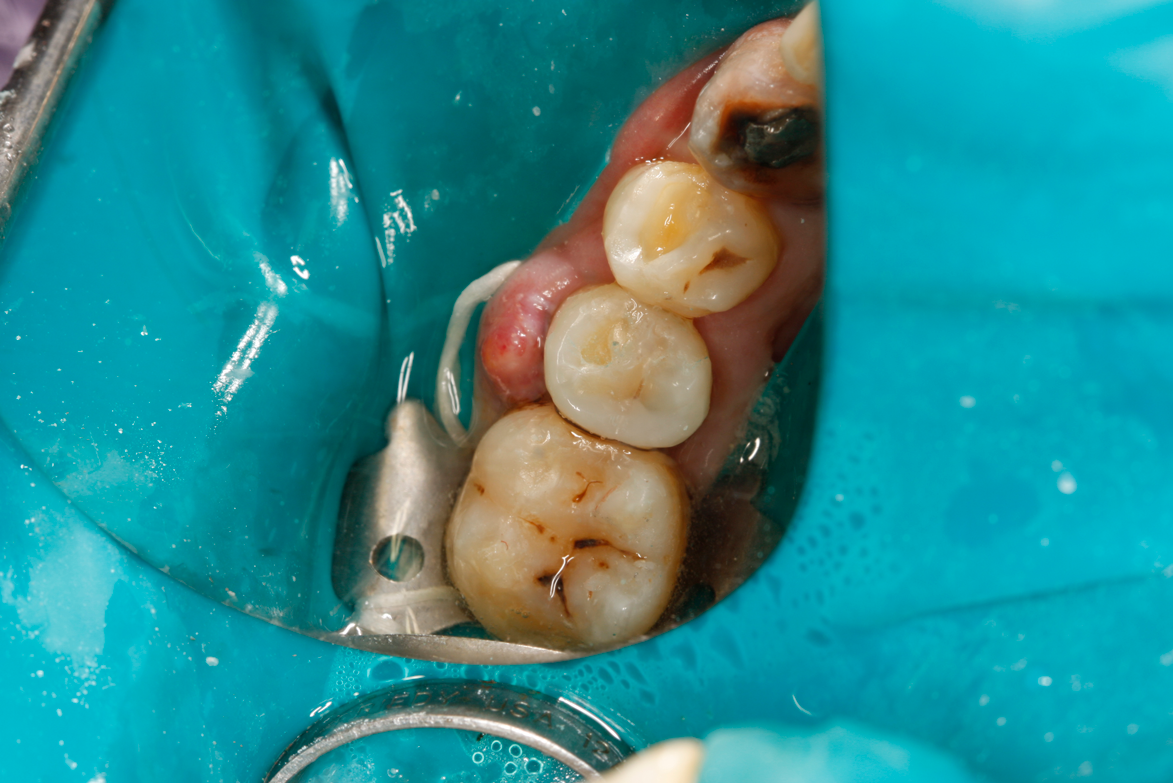

Fig 32. Preparation is completed, caries are removed, sand blasting with potassium carbonate is performed, and matrix band is placed.

Figure 32

A deep distal occlusal preparation was performed and a matrix band (Paraband, Practicon) was placed again, such that no wedge needed to be placed (Figure 32). The Groman Etchmaster was utilized to remove biofilm as previously shown in Figure 12. A total etch technique with 37% phosphoric acid was employed (Figure 33), and after thorough rinse and damp dry, a universal adhesive (Scotchbond Universal, 3M) with MDP was applied and light-cured 40 seconds at 1,200 mw/cm2 due to the depth of the box form (Fig- ure 34). Figure 35 shows the dual-cure bulk-fill flowable composite (Bulk EZ Plus, Zest Dental Solutions) being injected into the deep box with a 20-gauge bendable needle. It is important to keep extrusion pressure on the plunger while withdrawing the needle to prevent bubbles or voids in the composite interface with the tooth structure. Overfilling by approximately 10% and smoothing the surface only with brushes promotes good marginal seal (Fig- ure 36). It is critical to not disturb the occlusal surface of any dual-cure bulk-fill flowable with an attempt to "soft sculpt," as that may create marginal voids.